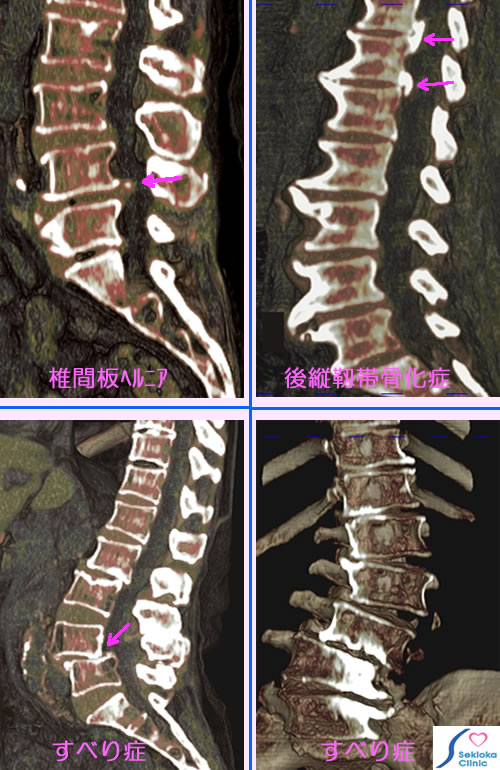

腰椎の病気: 腰痛、下肢痛

診断

神経の検査、X線撮影、CT。精査には腰椎の任意断面が観察できるMDCT、MRIが有用です。